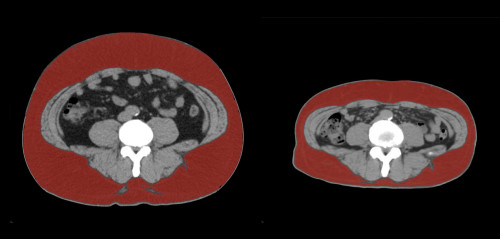

④

50代・男性(ご本人のご厚意で画像提供)

治療内容:チルゼパチド7.5mgの週1回自己注射による脂肪減少と脂肪肝改善

治療期間: 12ヶ月(52週)((用量は2.5mgから開始し最大で15mg。減量効果が得られる必要用量には個人差があります。))

費用:自由診療の場合は9900円(税込)×52(週)=514800円

想定されるリスク・副作用:下記に副作用を記載

※医療広告ガイドラインに準拠して表記

1:脂肪の減少

皮下脂肪の減少(赤色部分)